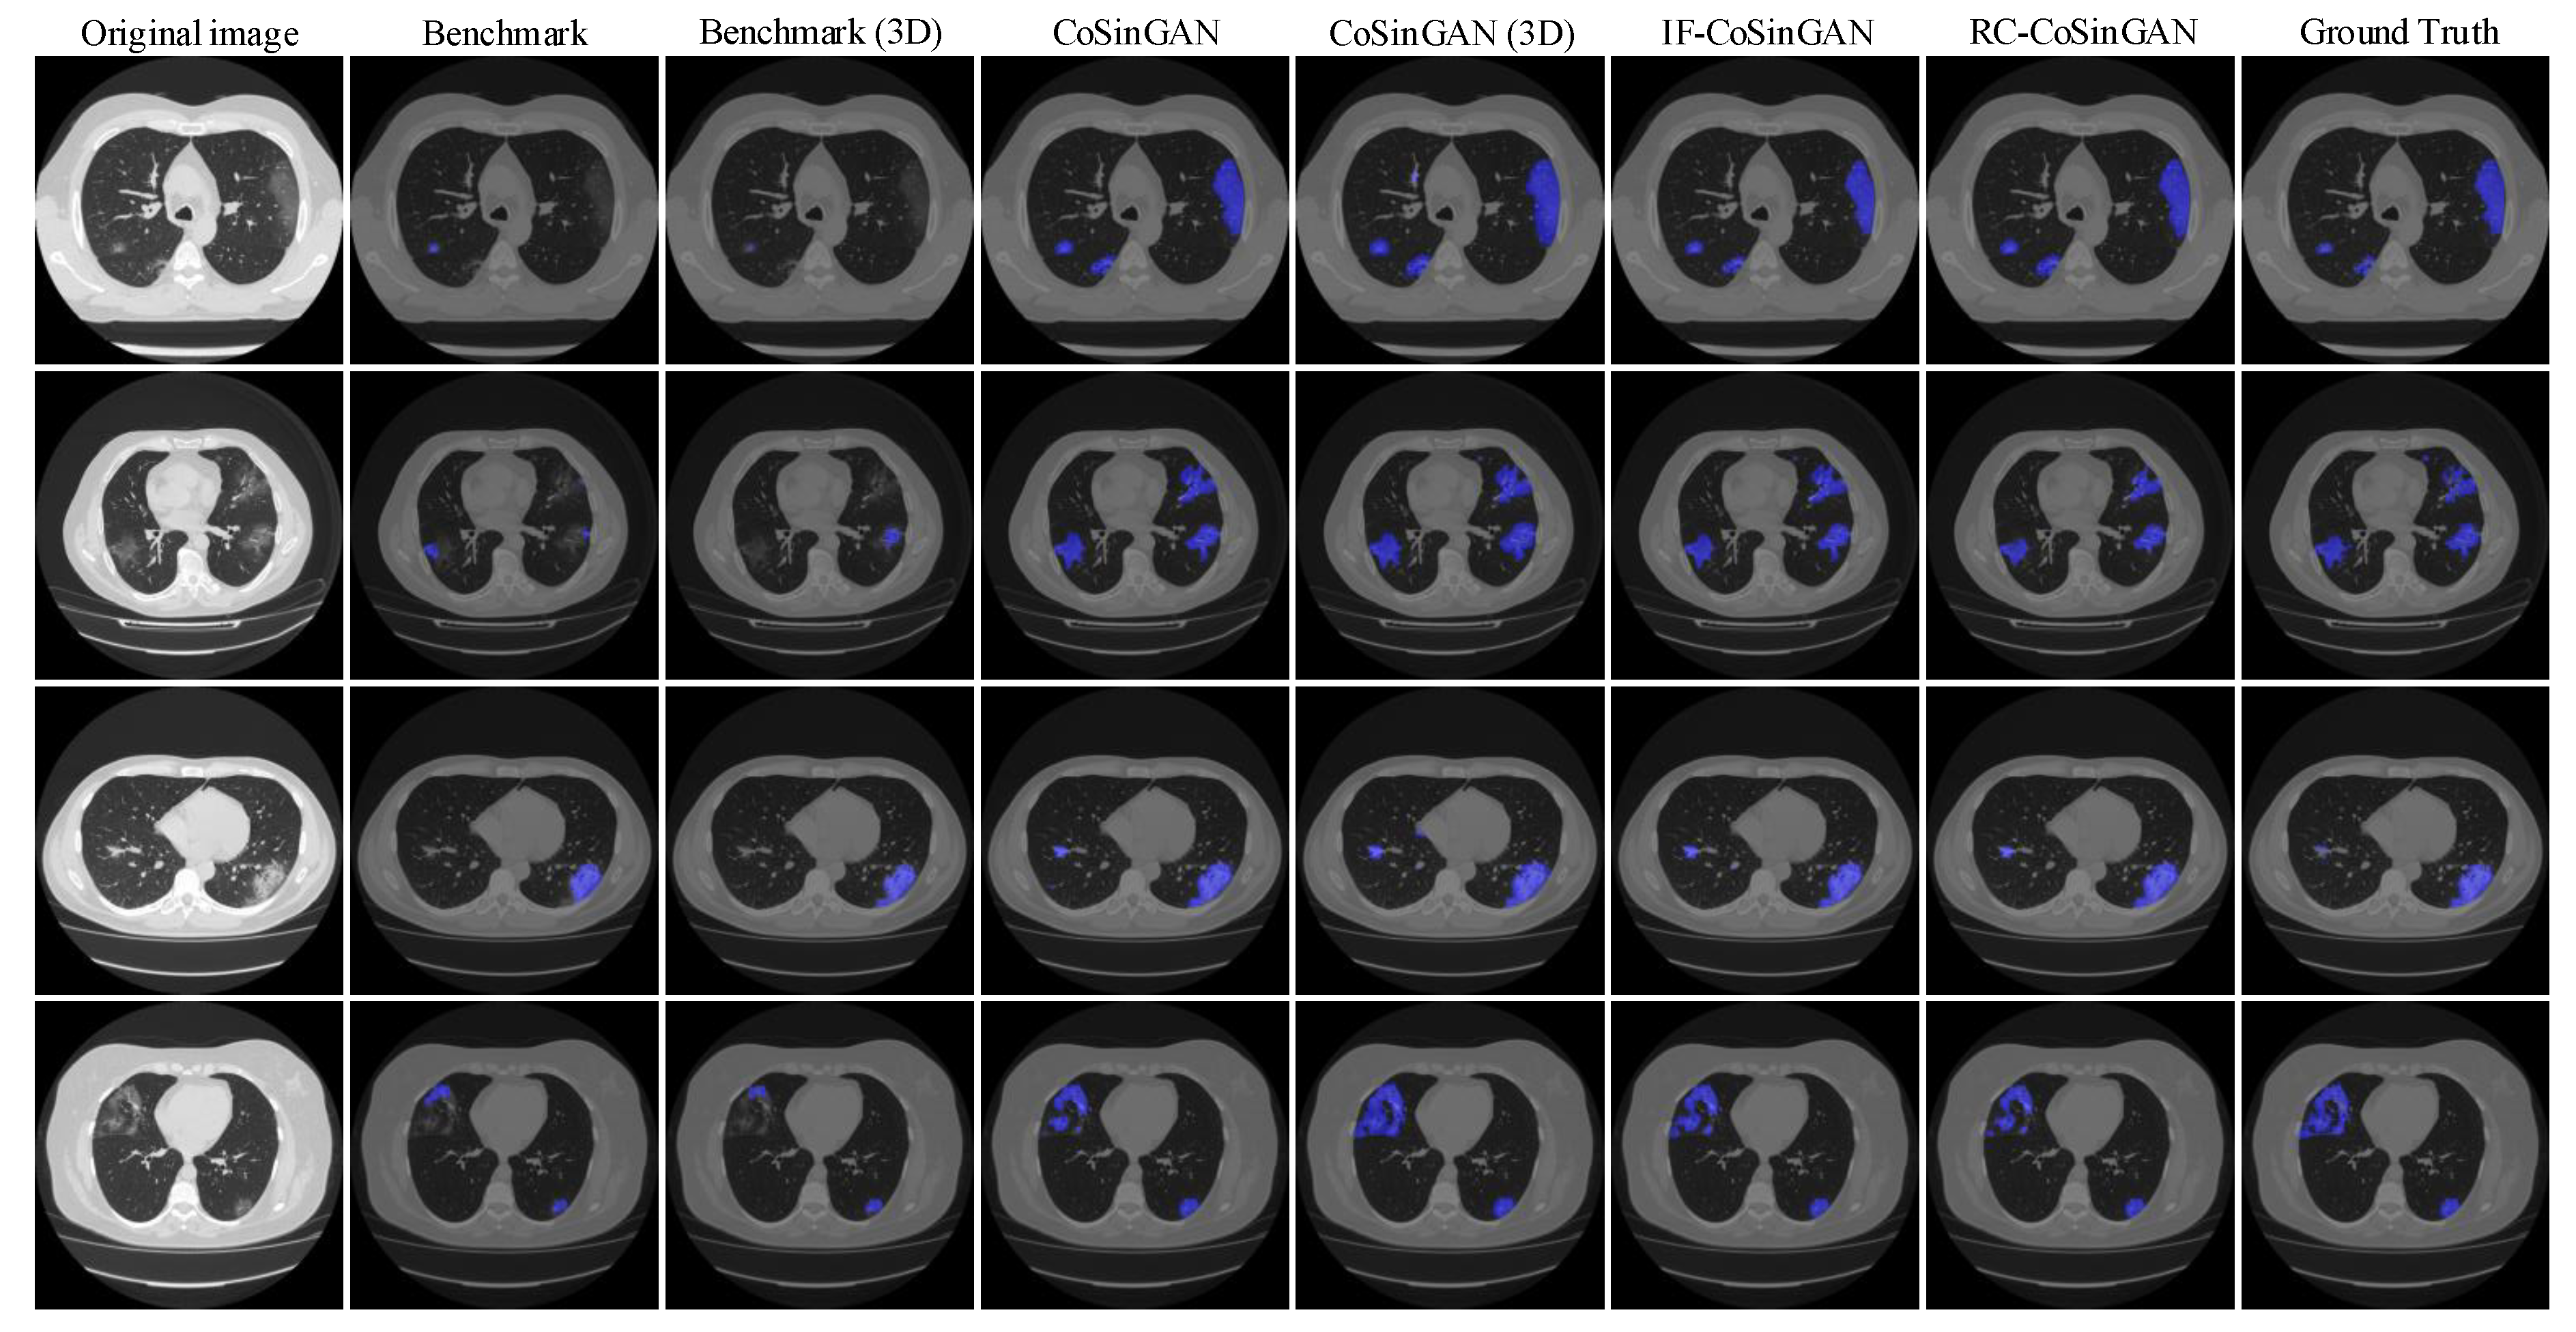

- Qualitative comparison